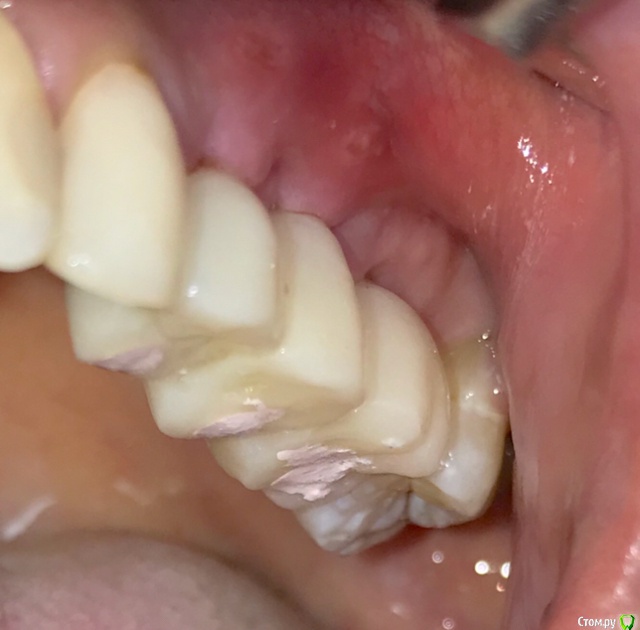

колесников Опубликовано 27 сентября, 2019 Автор Поделиться Опубликовано 27 сентября, 2019 Улучшение объема и качества мягких тканей в пришеечной области у ранее поставленных имплантов ,посредством тоннельной костной пластики. Объём 0,5г. Вид через 6 мес. 3 Ссылка на комментарий